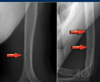

Osteoid Osteoma

Age: Adolescent 10-25 Oval lytic lesion (“lucent nidus”) surrounded by dense sclerotic cortical bone (“periosteal reaction”). Most Classic Locations: FEMORAL NECK 1. Meta/diaphysis of long bones (femoral neck = Most common) 2. Posterior elements of the spine Tx: percutaneou RF ablation

Osteoid osteoma MRI

“large amount of edema for the size of the lesion.”